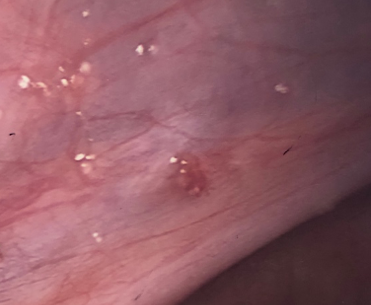

/In this picture you can see endometriosis mainly on the left uterosacral ligament, but close to the rectum.

There are numerous areas of endometriosis over the diseased peritoneum, but note the inflammation with bright red blood vessels coursing out from the classic dark lesions..

This endometriosis has been here for some time. There are small pink blisters, larger black areas, but also white areas representing scarring.